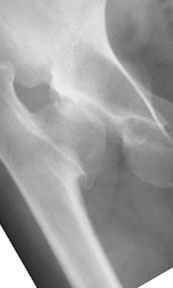

It appears that this patient has bilateral congenital hip displasia, as presented on the radiographs. As shown, the problem involves both sides of the hip joint: the acetabulum and proximal femur.

This patient is noted to have a very vertical joint surface orientation, as well, with retroversion of the acetabulum.

In a hip with normal version, (on discussion list) Hip Pain (Dr.Kullerkann) the lines connecting the anterior and posterior acetabular wall as seen on an AP radiograph usually intersect at one point near the superior and lateral portion of the acetabulum. As an example of an abnormal hip, a patient with a retroverted acetabulum will show the figure 8 pattern, with the two shadows crossing over the femoral head. In this particular patient, again it appears that there is a significant amount of retroversion of the acetabular wall, as the anterior wall appears to be more anteriorly displaced than in a normal hip.

In this patient, it appears that addressing either the femur or the acetabulum will be insufficient to help correct this patient’s problem. It would be necessary to approach both sides of the hip joint to correct the hip dysplasia.